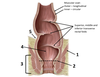

1? 2?

5? 6? 7?